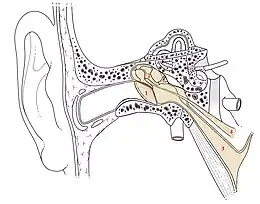

Caisse du tympan

C'est une cavité aplatie entre le méat acoustique externe et le labyrinthe osseux. Elle est constitutive de l'oreille moyenne. En forme de lentille biconcave, elle présente une paroi latérale tympanique et une paroi médiale labyrinthique.

Sa circonférence est constituée de :

- sa paroi supérieure ou tegmen tympani, mince et partagée par la suture pétro-squameuse supérieure ;

- sa paroi inférieure ou plancher de la caisse qui surmonte la base du processus styloïde ;

- sa partie postérieure ou mastoïdienne qui communique avec l’antre mastoïdienne par l’aditus ad antrum ;

- sa paroi antérieure ou tubo-carotidienne qui porte l’orifice postérieur ou tympanique de la trompe d'Eustache.

La cavité tympanique comporte :

- l'étage supérieur ou attique : le corps du marteau et de l'enclume ;

- l'étage inférieur ou atrium : le manche du marteau, la longue apophyse de l'enclume et l'étrier avec le récessus hypotympanique.

Labyrinthe osseux

C'est l'ensemble des cavités osseuses creusées dans le rocher et communicantes, constitutives de l'oreille interne :

- la cochlée (1) ;

- le vestibule (2) ;

- les canaux semi-circulaires (3 externe - 4 supérieur - 5 postérieur).

On lui rattache le méat acoustique interne.